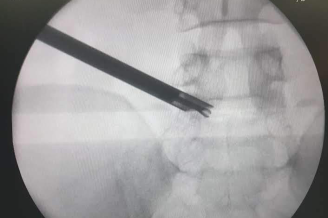

A transforaminal endoscopic discectomy provides the option to remove the prolapsed disc fragment through a different route, avoiding surgery through the scar tissue as well as the need to resect more bone, thereby preventing the need for a stabilisation and fusion.

Transforaminal endoscopic discectomy in a patient with post-laminectomy recurrent disc prolapse